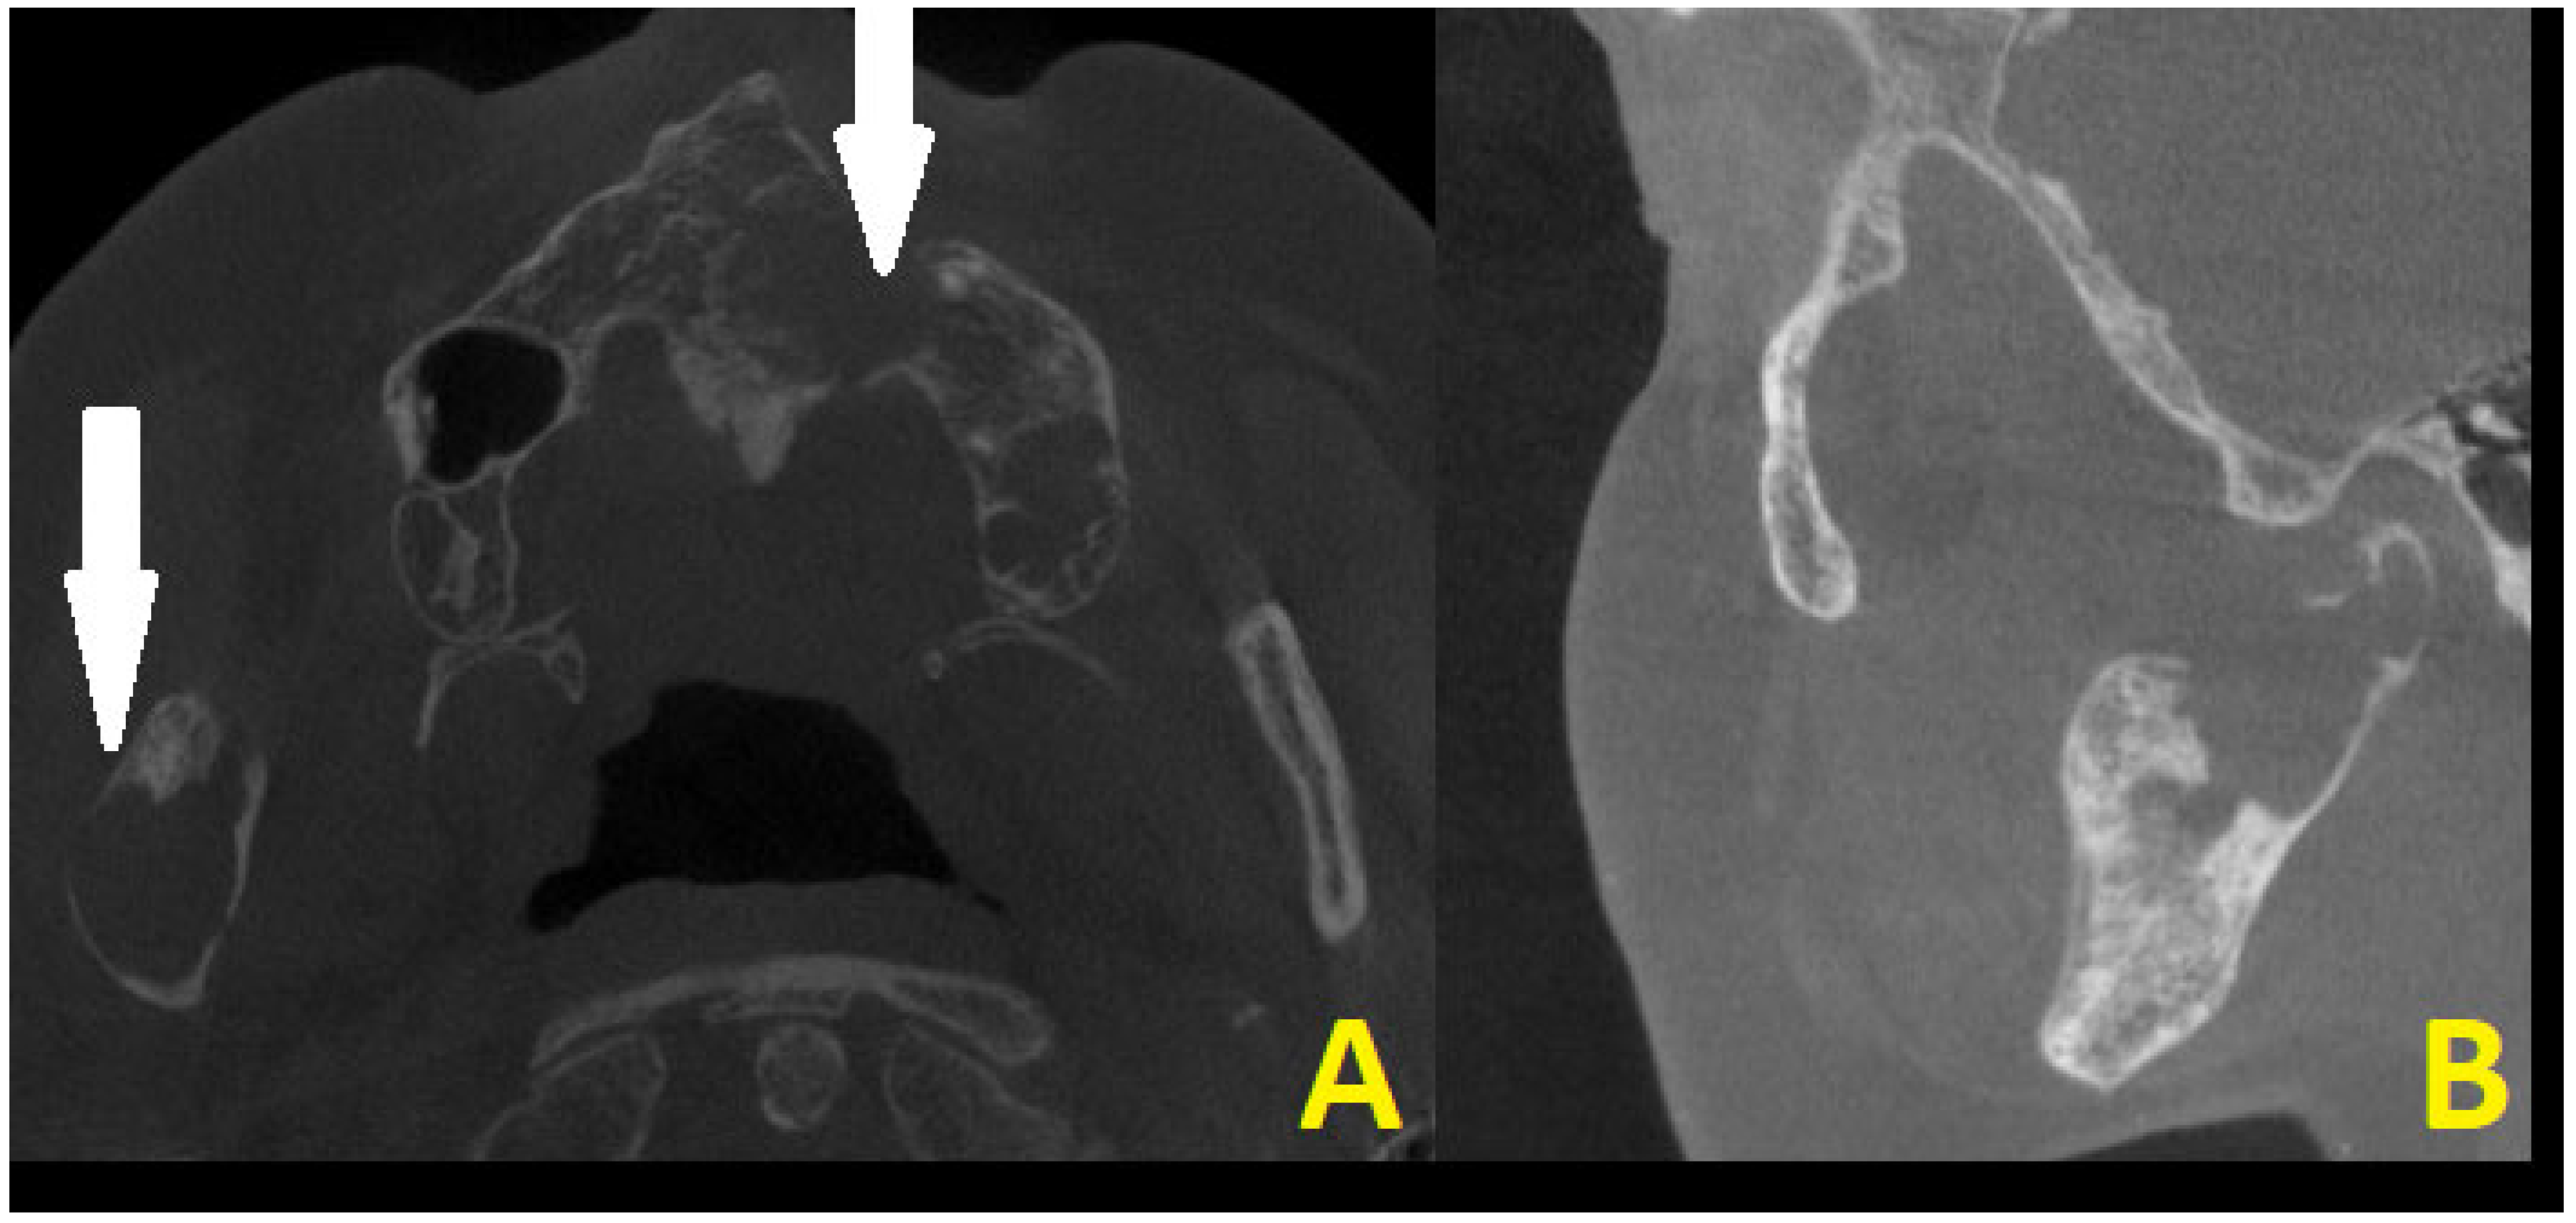

Figure 3. CBCT scans in axial projection (A) with maxillary destruction and sagittal (B) visualization of the cystic destruction of the right condylar process and condylar head. Cystic destruction of the left maxillary bone with an extra bone spread towards the lip and nasal cavity, and right mandibular ramus swelling with proliferation towards the condylar head is noted (white arrows). In surgical planning, the condition of the bone is very important for a good radiological bone evaluation, as well as for cortical bone estimation. Secondly, each surgery must maintain each patient’s quality of life (QOL). In the case of a 69-year-old patient, the most troublesome factors were related to an inability to fully open their mouth, the occurrence of transient pain, inflammation, the presence of right preauricular swelling, and the deterioration of chewing and biting ability. The first surgery step was used to remove all small lesions, fill them with allogenic bone grafts, and perform a right-sided coronoidectomy with cyst removal and decompression to prepare the right condyle for the second stage of surgery. The main troublesome course of surgery included the necessity to remove part of the bone TMJ structures affected by the disease and reconstruct the TMJ for the best possible outcome to enable the elderly lady to be able to properly open her mouth, eat, and speak. Because of this patient’s economic means and a great fear of a total TMJ artificial endoprosthesis, a decision was made to reduce both the costs and scope of surgery, meaning a reduction in the usage of many materials and foreign body components from a custom-made TMJ endoprosthesis. Secondly, since the OKC did not do any destruction within the condylar fossa, the articular disc and TMJ joint were healthy, so the usage of an acetabulum, namely the glenoid fossa alloplastic component, was not necessary. Planning a good CBCT is enough to plan the scope of bone resection and removal of all polycystic lesions from the right mandibular head, condyle, and part of the ramus. Because of the locally aggressive character of OKC, their extracortical spread, polycystic occurrence, and joint manifestation, a decision was made for more aggressive surgery with immediate joint reconstruction in the second stage of surgery when mouth opening was improved. Both surgeons (K.N., K.Ł.) decided to improve the overall mouth opening and excise all advanced aggressive OKC lesions at first, and then decide on the scope for TMJ surgery to improve occlusion and bite, and prepare for further patients’ prosthodontic treatment. No necessity for additional CT, MRI, or similar studies was needed.